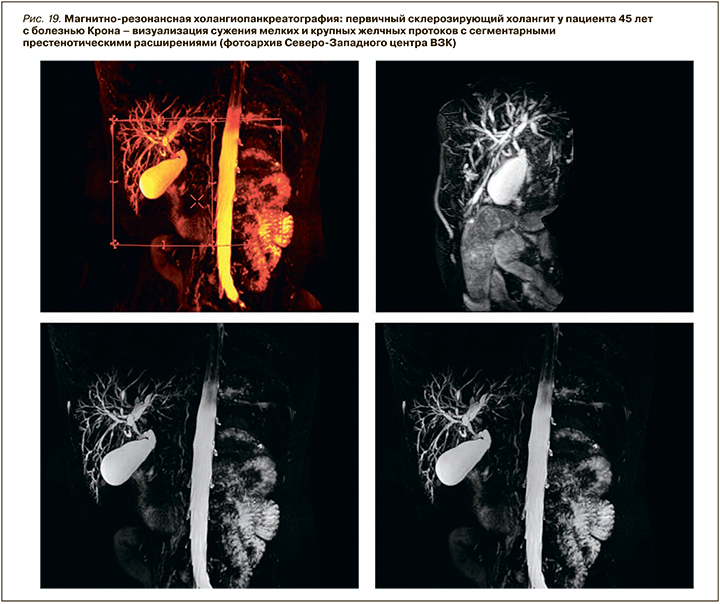

В нашей когорте пациентов с ВЗК вовлечение печени было диагностировано у 8,2% человек – с большей частотой при язвенном колите (5,3%) и меньшей при болезни Крона (2,9%). В структуре всех поражений печени преобладала неалкогольная жировая болезнь печени (НАЖБП) – 54,7% (4,5% среди пациентов с ВЗК), в 5,2% случаев был верифицирован АИГ (0,43% среди пациентов с ВЗК), в 12,6 % (1,1% всей когорты) – ПСХ (рис. 18, 19).

По литературным данным, ПСХ – классическое внекишечное проявление, ассоциированное с ВЗК, но не связанное с активностью воспалительного процесса в кишке. Это хроническое аутоиммунное холестатическое заболевание печени с диффузным воспалением и фиброзом внутри- и внепеченочных желчных протоков, их облитерацией с формированием мультифокальных билиарных стриктур. ПСХ характеризуется прогрессирующим течением, приводящим к развитию цирроза печени и печеночной недостаточности. У пациентов с ВЗК он обнаруживается в 2–8% случаев при язвенном колите и в 1–3% при болезни Крона. При этом у 60–80% пациентов с ПСХ отмечается его ассоциация с ВЗК, причем чаще с язвенным колитом – более чем в 75–80% случаев. Оставшиеся 20–25% приходятся на долю болезни Крона или неклассифицируемого колита (около 5%) [72 ,73].